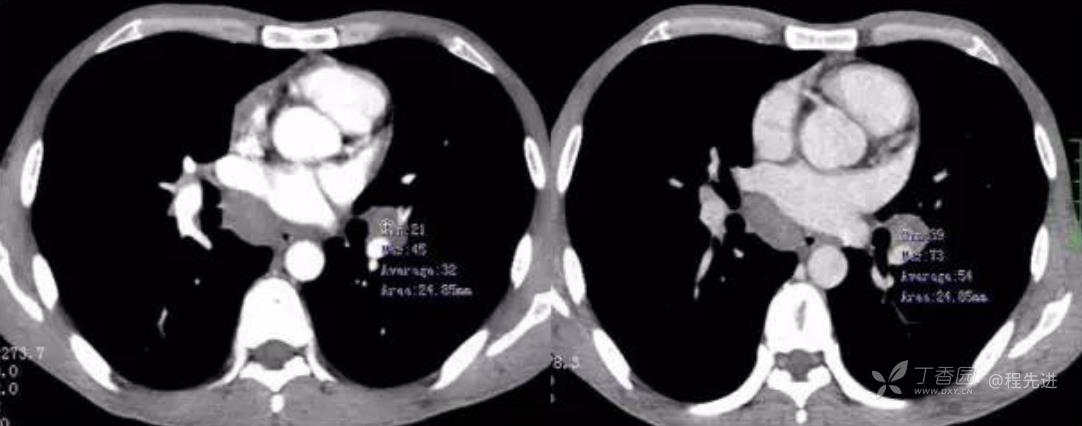

静脉期

动脉期CT值32HU,静脉期CT值54HU

左动脉期,右静脉期